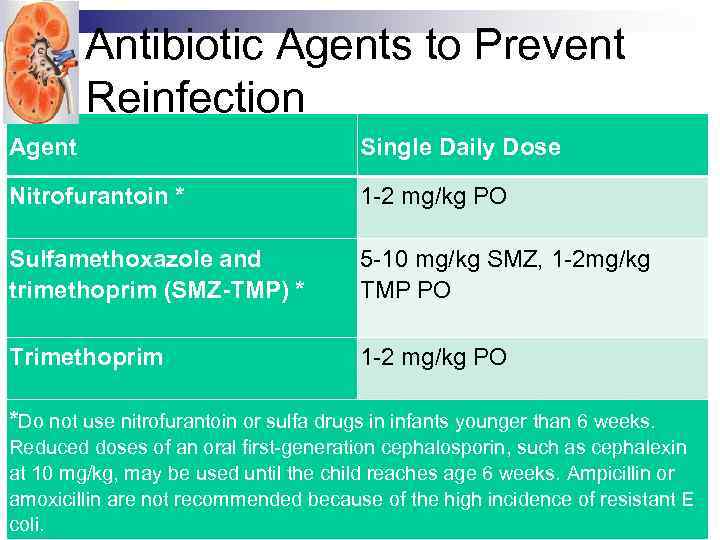

Antibiotic Agents to Prevent Reinfection Agent Single Daily Dose Nitrofurantoin * 1 -2 mg/kg PO Sulfamethoxazole and trimethoprim (SMZ-TMP) * 5 -10 mg/kg SMZ, 1 -2 mg/kg TMP PO Trimethoprim 1 -2 mg/kg PO *Do not use nitrofurantoin or sulfa drugs in infants younger than 6 weeks. Reduced doses of an oral first-generation cephalosporin, such as cephalexin at 10 mg/kg, may be used until the child reaches age 6 weeks. Ampicillin or amoxicillin are not recommended because of the high incidence of resistant E coli.

Antibiotic Agents to Prevent Reinfection Agent Single Daily Dose Nitrofurantoin * 1 -2 mg/kg PO Sulfamethoxazole and trimethoprim (SMZ-TMP) * 5 -10 mg/kg SMZ, 1 -2 mg/kg TMP PO Trimethoprim 1 -2 mg/kg PO *Do not use nitrofurantoin or sulfa drugs in infants younger than 6 weeks. Reduced doses of an oral first-generation cephalosporin, such as cephalexin at 10 mg/kg, may be used until the child reaches age 6 weeks. Ampicillin or amoxicillin are not recommended because of the high incidence of resistant E coli.